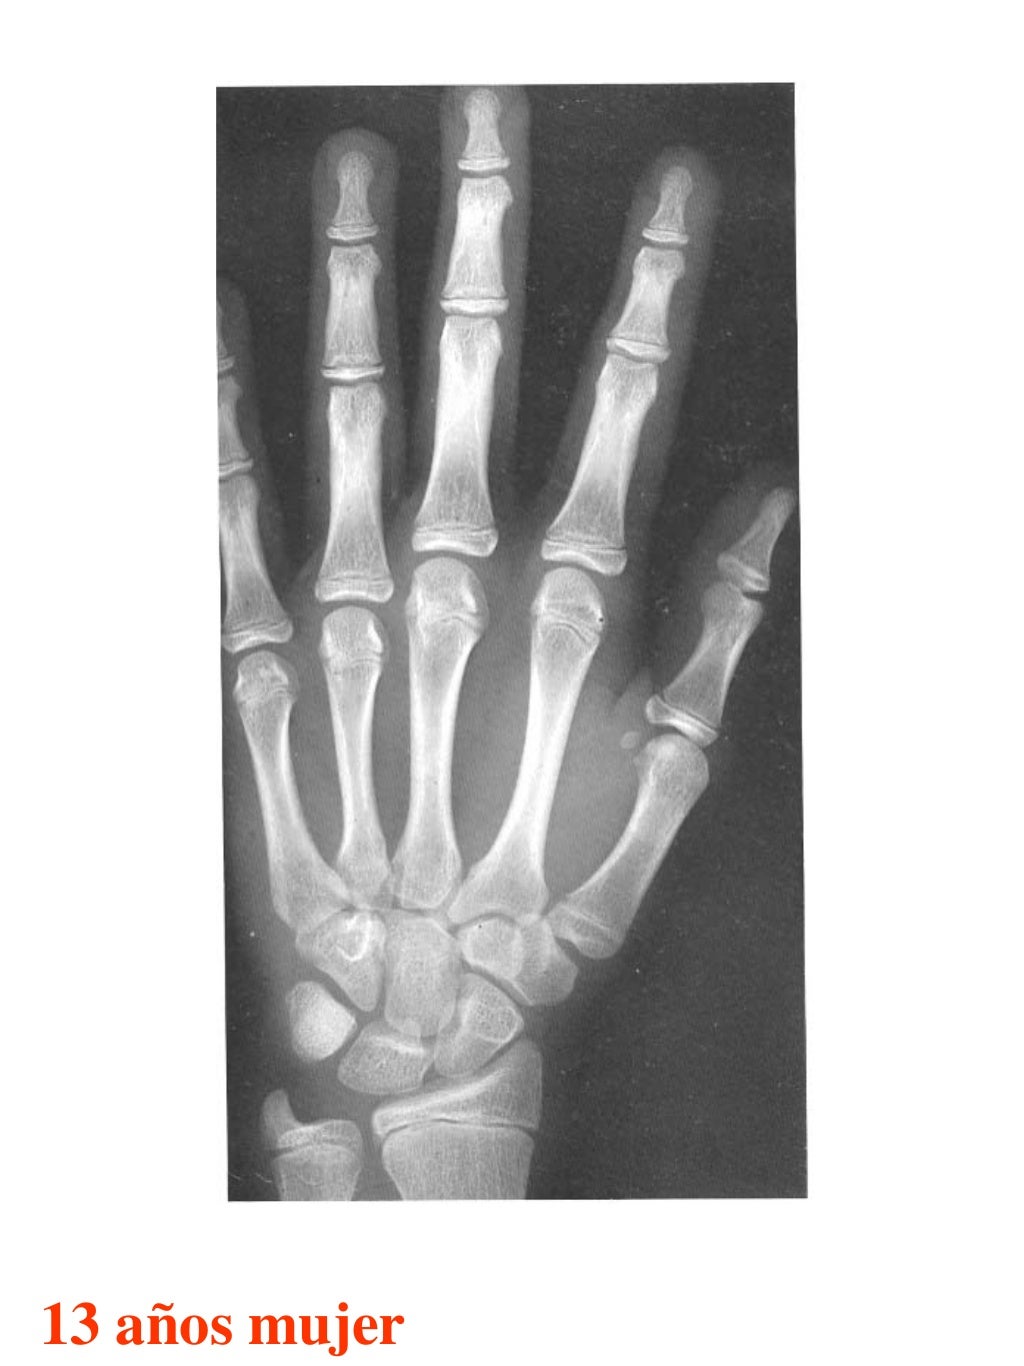

Tablas De Greulich Y Pyle . Scribd is the world's largest social reading and publishing site. This systematic review summarizes the. The radiographic atlas of skeletal development of the hand and wrist by ww greulich and si pyle is a classic radiological. The standards established by greulich and pyle, undoubtedly the most popular method, consist of two series of standard plates. The greulich and pyle method is one of the two main ways to assess the bone age of children. El documento lista las edades. Both main methods of bone age. 153 recomendaciones • 616,869 vistas. Atlas greulich y pyle | pdf | descarga gratuita. The greulich and pyle atlas is used to estimate the age of children and adolescents.

Tablas De Greulich Y Pyle The standards established by greulich and pyle, undoubtedly the most popular method, consist of two series of standard plates. The standards established by greulich and pyle, undoubtedly the most popular method, consist of two series of standard plates. El documento lista las edades. This systematic review summarizes the. The greulich and pyle method is one of the two main ways to assess the bone age of children. Both main methods of bone age. Scribd is the world's largest social reading and publishing site. 153 recomendaciones • 616,869 vistas. Atlas greulich y pyle | pdf | descarga gratuita. The greulich and pyle atlas is used to estimate the age of children and adolescents. The radiographic atlas of skeletal development of the hand and wrist by ww greulich and si pyle is a classic radiological.